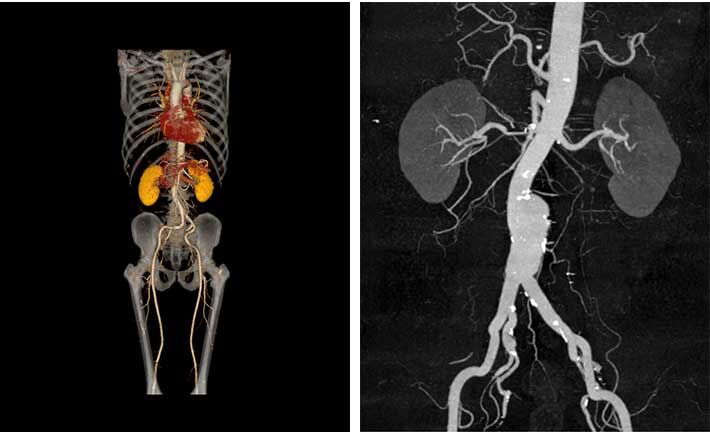

VR、MPR、CPR、MIP、AIP、MinIP、SSD and other image;

Automatic bone removal, bed plate removal;